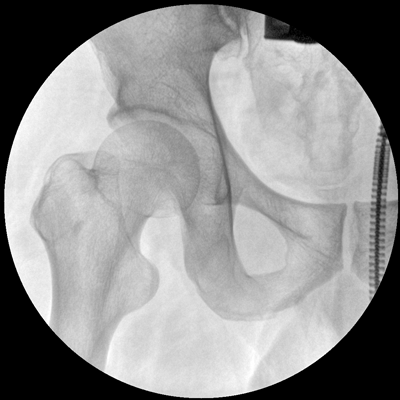

小巧輕便 超凡靈動(dòng) PLX C1116

●全數(shù)字化百萬(wàn)像素影像系統(tǒng),圖像清晰